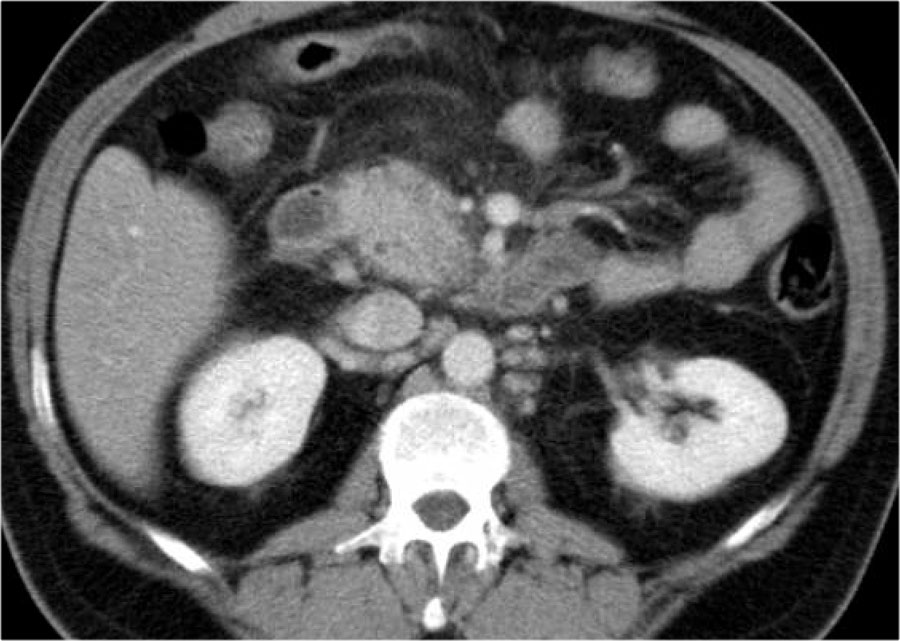

Các dấu hiệu bao gồm:

- Tụy ngấm thuốc bình thường toàn bộ.

- Các ổ dịch quanh tụy lan rộng, có tỷ trọng dạng lỏng và không lỏng trên CT.

- Có ít nhất hai ổ dịch, nhưng không có hoại tử nhu mô tụy (CTSI: 4).

- Vào ngày thứ 18, các ổ dịch quanh tụy mở rộng và xuất hiện thành không hoàn toàn.

Vào ngày thứ 5, ổ dịch này có thể được chẩn đoán là ổ hoại tử cấp tính có khả năng cao.

Vào ngày thứ 18, thành chưa hoàn toàn, nhưng có thể dự đoán rằng trong vài ngày tới đây sẽ trở thành ổ hoại tử được bao bọc với thành hoàn chỉnh.